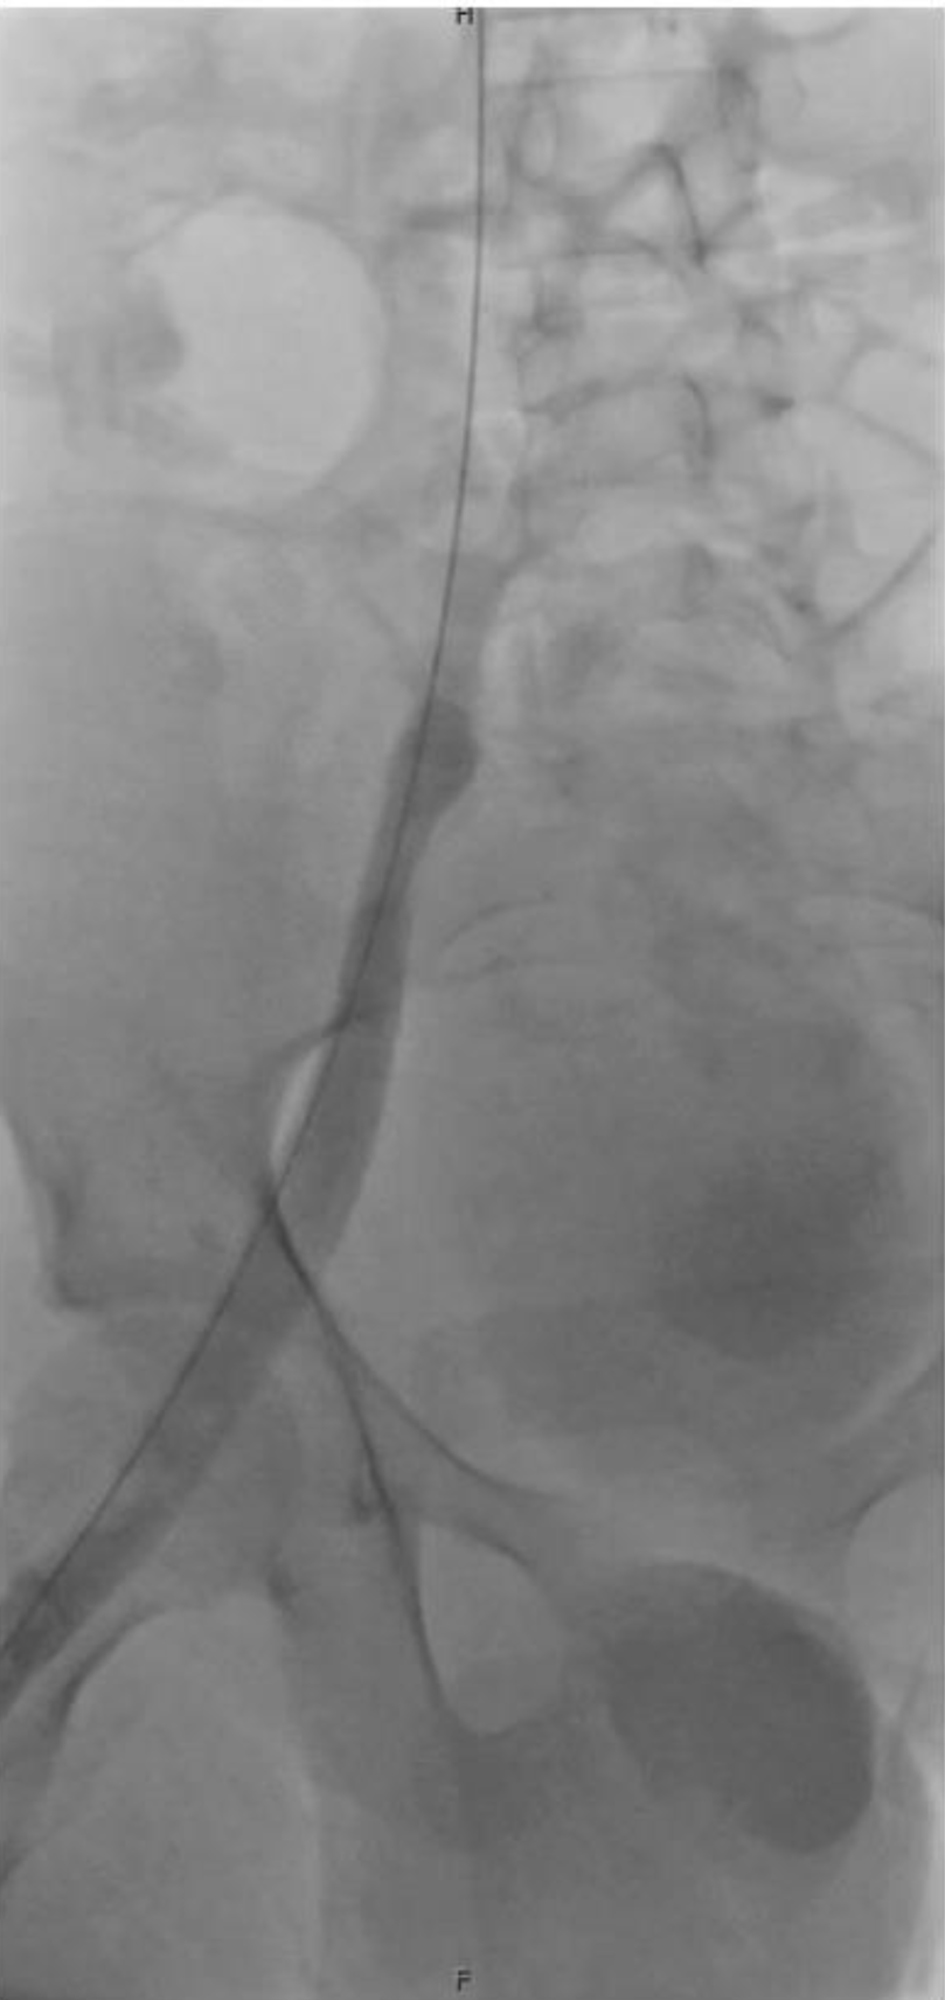

At an outside hospital, computed topography (CT) angiography revealed right lower extremity DVT extending from the femoral vein to the foot, along with bilateral lower lobe pulmonary emboli (PEs) (Fig. 1). Laboratory studies were notable for leukocytosis (white blood cell (WBC) 23), significant anemia (hemoglobin 5.3 g/dL), and thrombocytosis (platelets 700). He received one unit of packed red blood cells (pRBCs) prior to transfer and a second unit upon arrival at Nationwide Children’s Hospital. Initial vital signs were temperature 99.2 °F (37.3 °C), pulse 123 bpm, respirations 24, blood pressure 125/87 mm Hg, and oxygen saturation 100% on 2 L of O2 for comfort. On physical exam, he was ill-appearing and tachycardic with dry mucous membranes, pale skin, and delayed capillary refill. Though not in respiratory distress, he was tachypneic with diminished breath sounds at the bases. His right leg was diffusely swollen, plethoric, and extremely tender with intact distal pulses. An electrocardiogram (ECG) showed sinus tachycardia (heart rate (HR) 118), left axis deviation, T-wave inversion in V1, and right bundle branch block. There were no prior ECGs for comparison. B-type natriuretic peptide and troponin levels were normal. An echocardiogram showed no evidence of right heart strain.

Click for large image

Figure 1. Computed tomography of the chest. Arrow points to one of many pulmonary emboli.